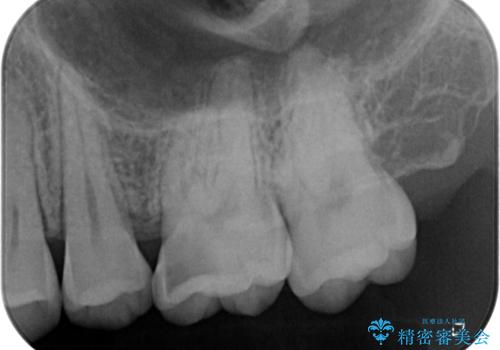

拡大鏡視野化にて、虫歯を除去し、セラミックインレー(セラミックの詰め物)に適した形に整えました。

見た目、噛み合わせともに満足していただけました。